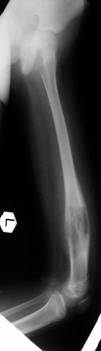

Pre Op

X-ray (Left femur)

osteolytic lesion

(?) osteosarcoma